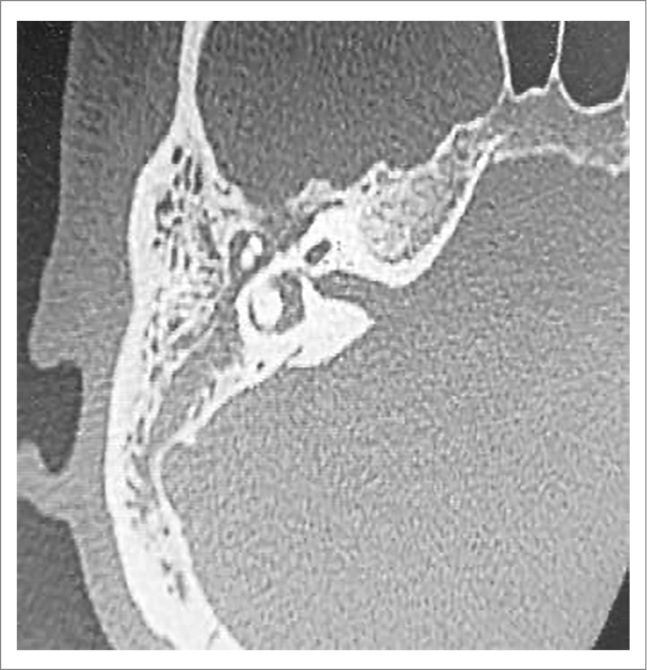

По данным мультиспиральной компьютерной томографии (МСКТ) височных костей с обеих сторон визуализировалось тотальное затемнение полостей среднего уха без деструктивных изменений, цепь слуховых косточек сохранна, прослеживается на всем протяжении (рис. 4, 5).

Рис. 4. КТ, аксиальный срез: тотальное затемнение полостей среднего уха без деструктивных изменений, цепь слуховых косточек сохранна, прослеживается на всем протяжении.

Рис. 5. КТ, аксиальный срез, правая височная кость: тотальное затемнение полостей среднего уха без деструктивных изменений, цепь слуховых косточек сохранна, прослеживается на всем протяжении.